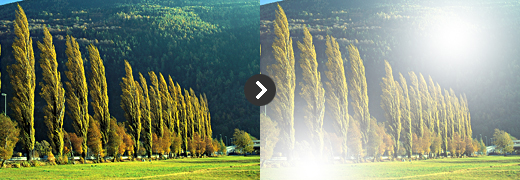

정상안 (물체가 선명하게 보인다)

정상안 (물체가 선명하게 보인다) -

백내장안 : 빛이 퍼진다 (물체가 흐릿하게 보인다)

백내장안 : 빛이 퍼진다 (물체가 흐릿하게 보인다)